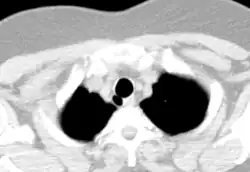

Divertículo traqueal visto na imagem axial da TC